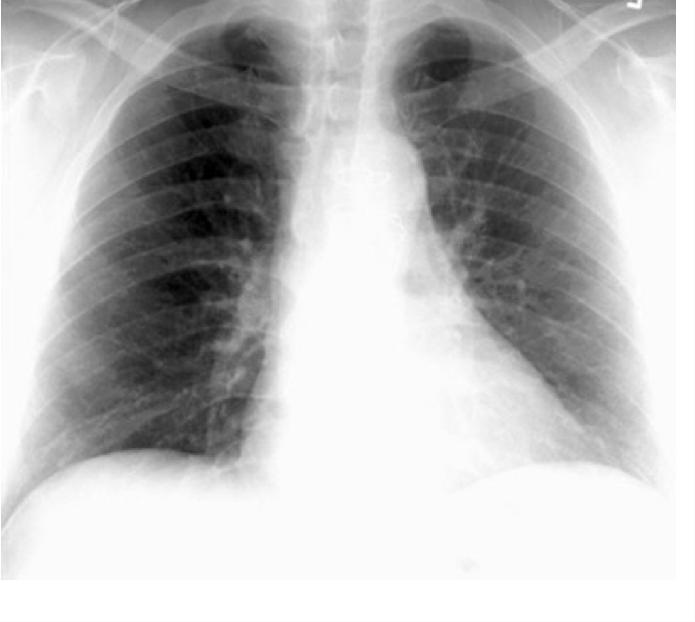

PA view

Beam goes back to front

AP view

beam goes front to back

PA vs AP

X-ray comparison

CXR- due to different densities of internal structures

can get a detailed exam of the lung parenchyma, pulmonary blood vessels, and of the heart